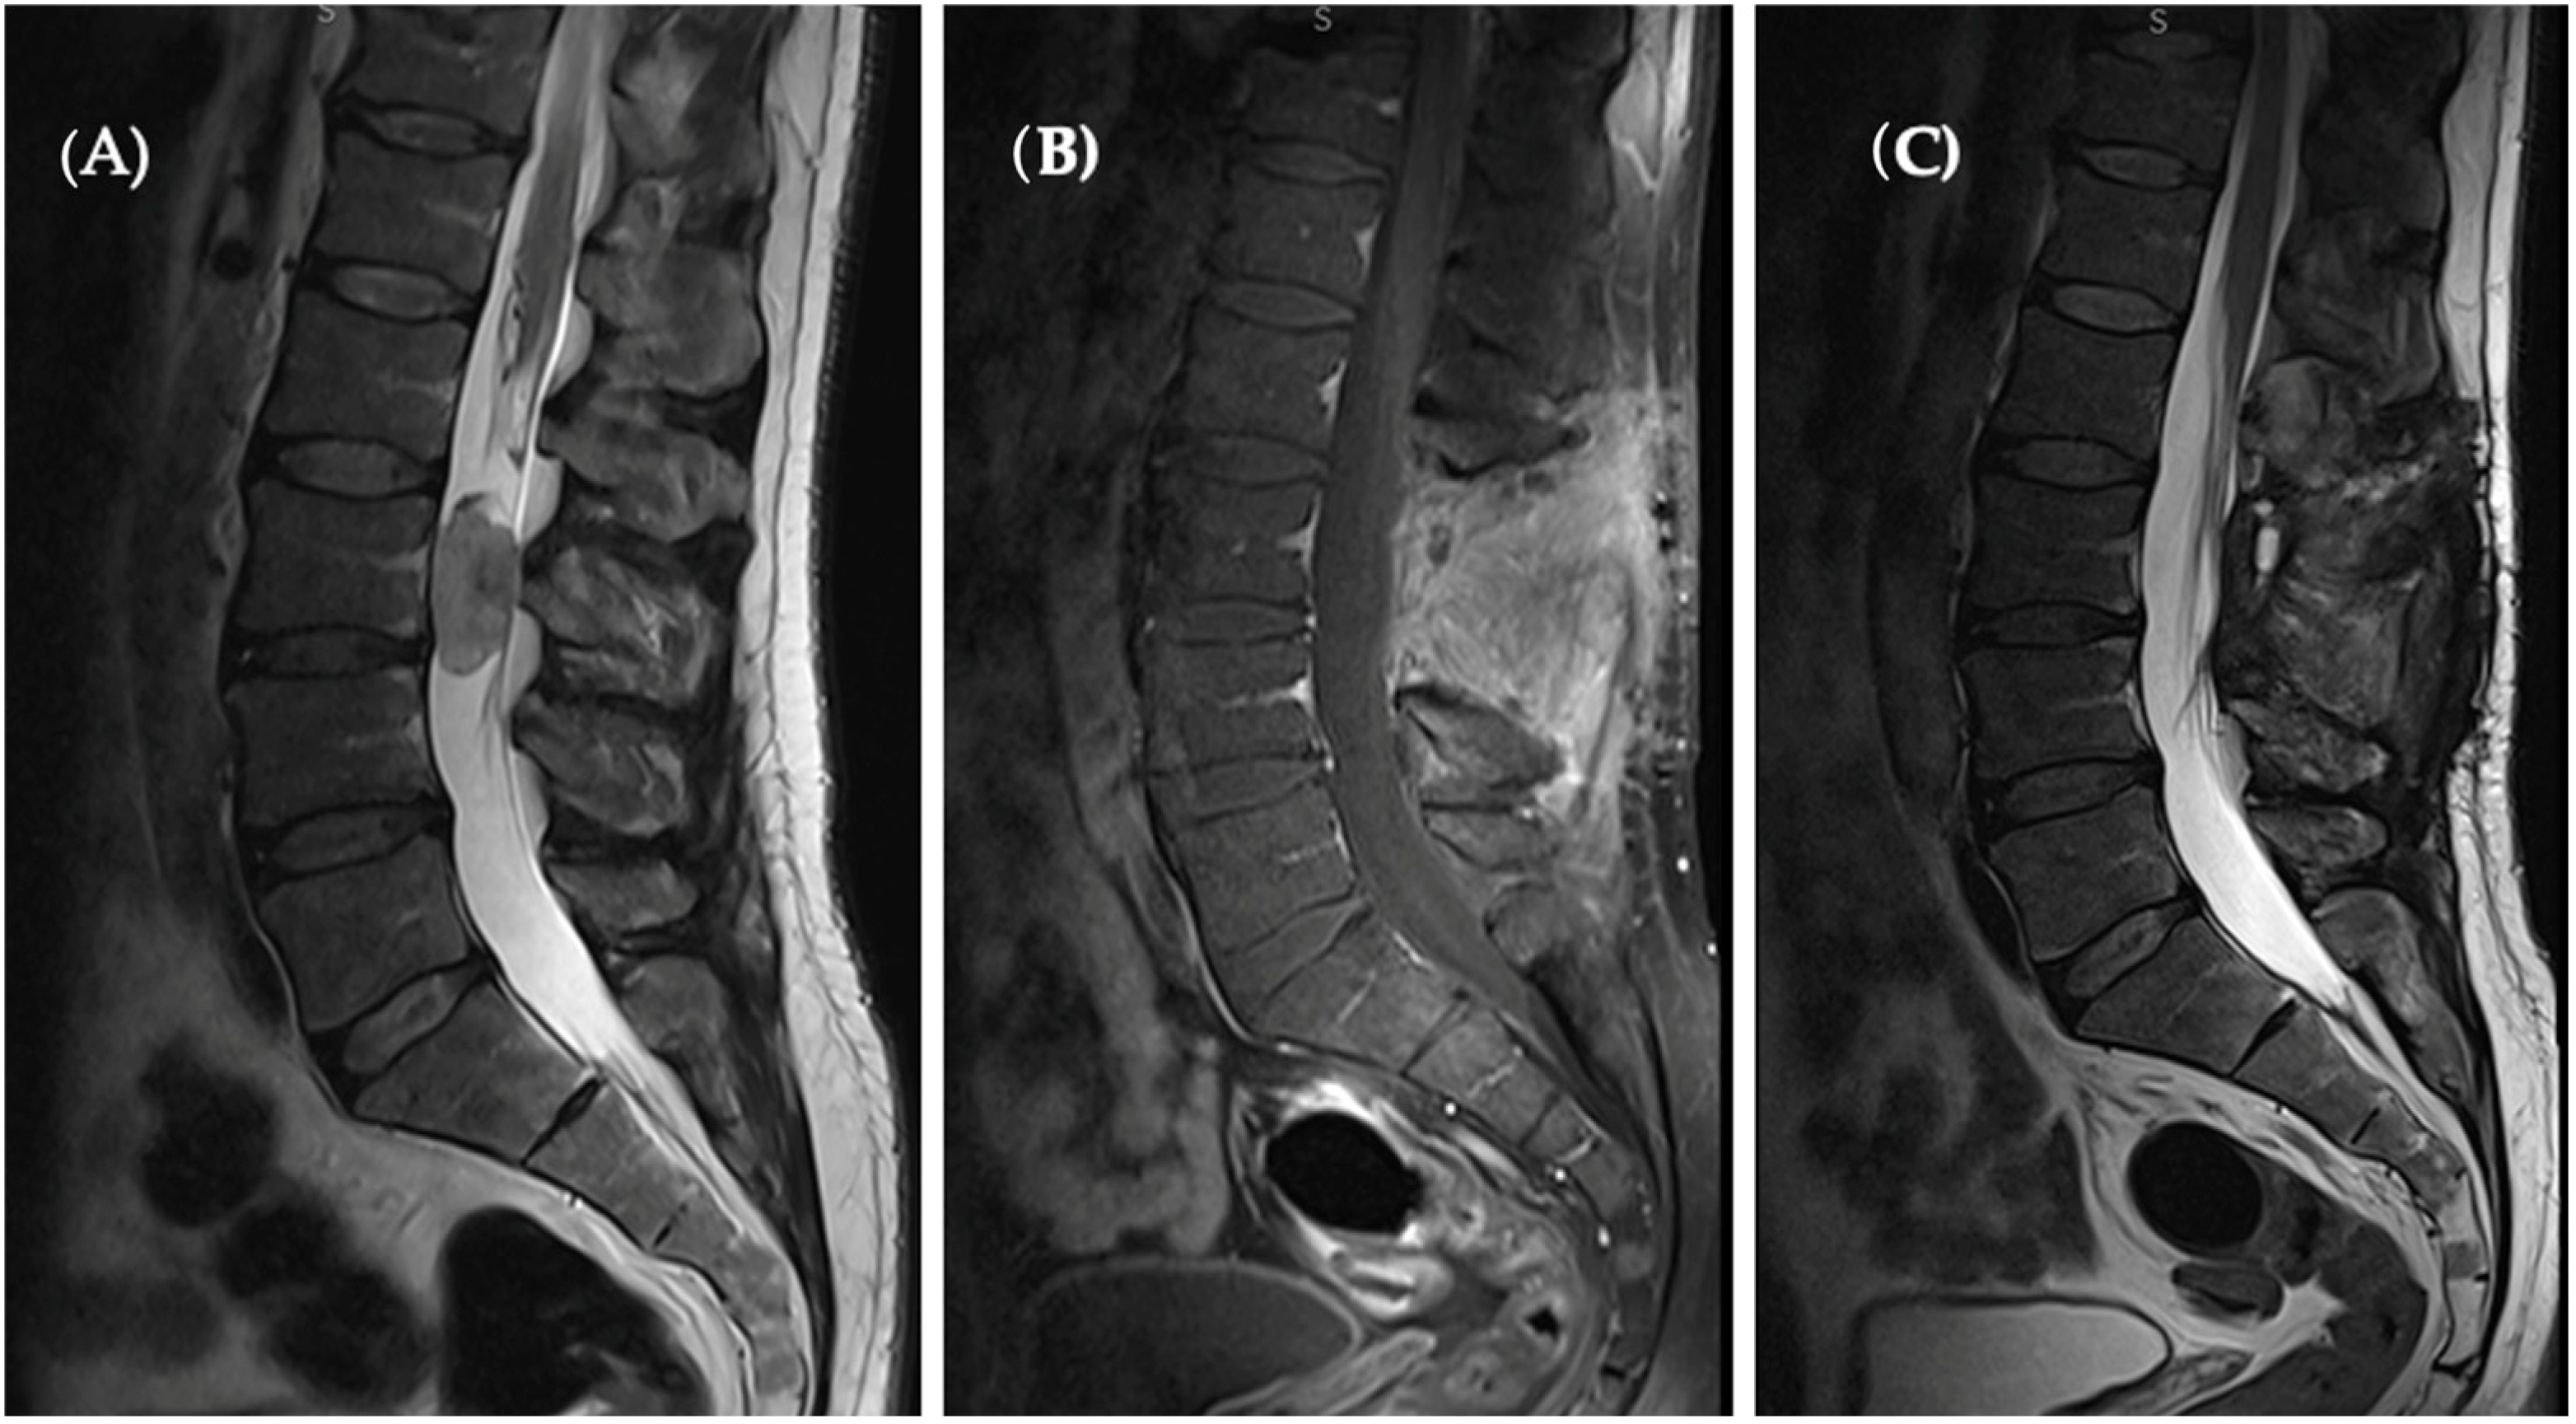

A 45-year-old male sought medical attention at our outpatient facility, reporting a progressive decline in locomotor function. Upon evaluation via magnetic resonance imaging (MRI), an oval-shaped intradural lesion was identified at the L3 vertebral level, occupying the spinal canal and exerting bilateral nerve root compression. Neurological examination revealed diminished lower extremity tendon reflexes and mild weakness in knee extension and hip external rotation, devoid of sensory deficits.

Subsequent MRI imaging undertaken after a one-year period displayed no evidence of tumor recurrence, precluding the necessity for adjuvant therapy (Figure 3).

Figure 3.

(A) Pre-op T2 sagittal MRI revealed a hyperintense oval-shaped lesion located at the L3 level occupying spinal canal. (B) Sagittal T1 with contrast enhanced as well as T2 sagittal. (C) Sections present a complete tumor removal and no sign of recurrence.